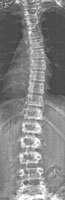

Возможность использования топографического мониторинга состояния больных сколиозом взамен рентгена была изучена на основе клинического материала школы-интерната №133 для детей больных сколиозом г.Новосибирска, где, начиная с 1995 года, проводились ежегодные обследования на ТОДП постоянного контингента больных параллельно с рентгеном. Среди больных по характеру течения заболевания выделены 3 группы: СФ - стабильная форма сколиоза, УПФ - умеренно прогрессирующая, БПФ - быстро прогрессирующая форма. Пример наблюдения больной с быстро прогрессирующей формой сколиоза приведен на рисунках ниже.

9,0 лет 10,4 лет 10,8 лет 11,4 лет 12 лет

PTI=1,0; Cobb=10° PTI=1,3; Cobb=17° PTI=1,9; Cobb=23° PTI=2,9; Cobb=38° PTI=3,6; Cobb=55°

За трехлетний период наблюдения в возрасте с 9 до 12 лет основная правосторонняя грудная дуга по углу Кобба спрогрессировала с 10 до 55°, т.е. средняя скорость прогрессирования составила 15° в год. Общий индекс нарушения формы дорсальной поверхности туловища PTI изменился с 1,0 (граница нормы и умеренно выраженных отклонений) до 3,6 (значительное отклонение). Следует обратить внимание, что в начале наблюдения туловище больной имело хороший баланс во фронтальной плоскости (вертикальная ось, проходящая через вершину межъягодичной складки, проходит также и через C7), а с возраста 10,8 лет стало явно нарастать нарушение баланса с отклонением туловища вправо, т.е. в сторону выпуклости основной дуги. Приведенный пример убедительно демонстрирует наглядность топографических данных и их большую информативность для решения задачи неинвазивного мониторинга состояния больных сколиозом.